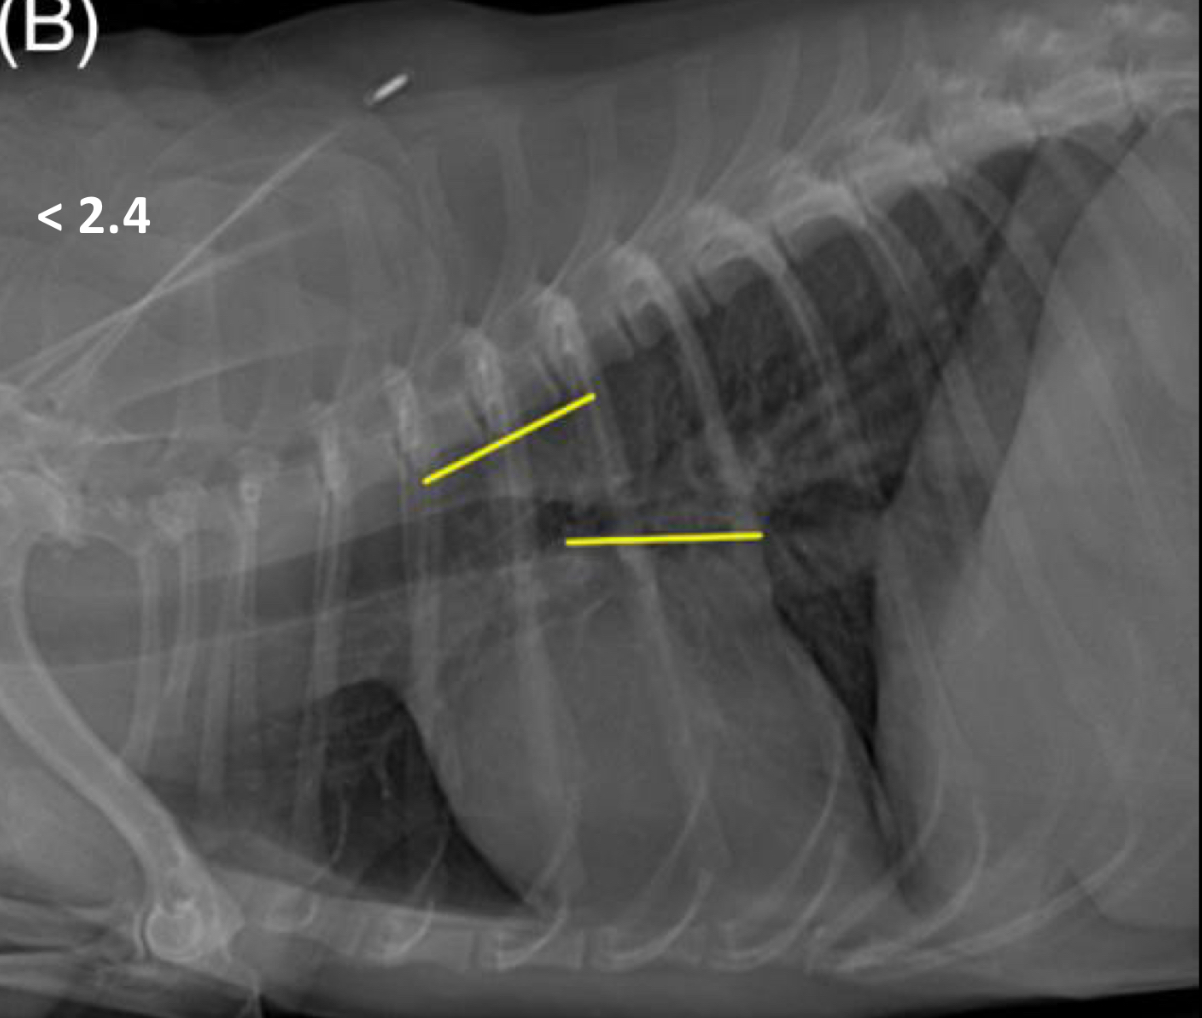

vertebral left atrial size should be < ______ vertebrae

2.4

pulmonary veins should be the same size as the ___ rib

9th